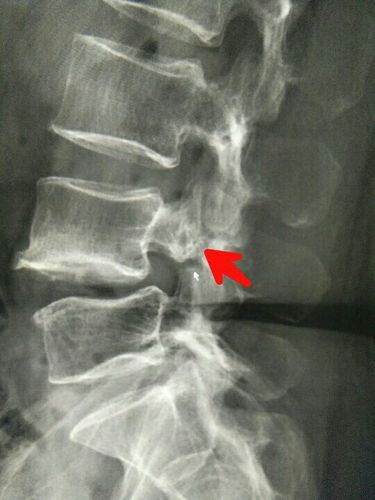

椎弓根断裂

椎弓根断裂,腰椎弓根断裂

腰4椎弓根崩裂

腰椎弓根断裂

椎弓根断裂图片

椎弓根骨折

椎弓根峡部